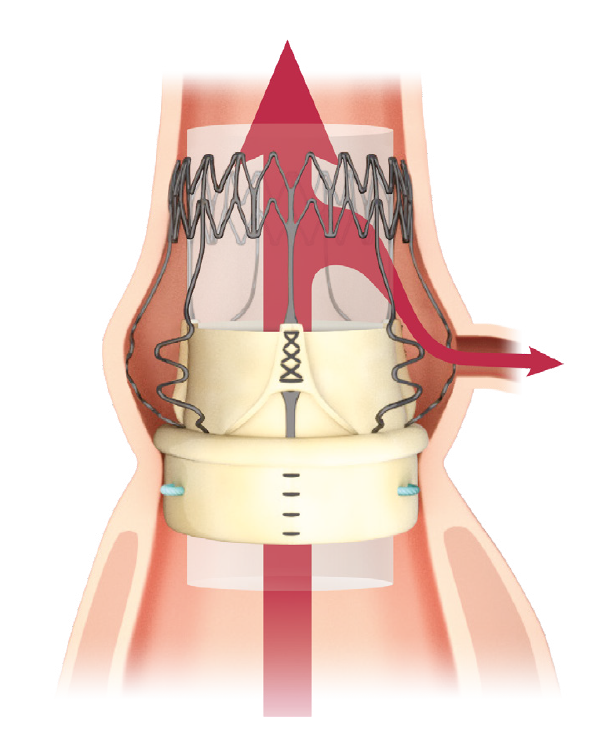

Designed for the future: the ideal docking station for Valve-in-Valve

Perceval Plus is a valve designed for the future. Not only is it durable,9 but it also gives patients even broader treatment options for their future. Its exclusive stent design allows even circumferential expansion to accommodate future transcatheter valves, making Perceval Plus ViV friendly by design. Thanks to its unique features, all patients eligible for biological AVR may benefit from a Perceval Plus implant.**12,13

Even circumferential expansion

The inflow ring can be evenly and circumferentially expanded up to 2.5mm above its nominal size, which allows for hemodynamic advantages and greater compatibility with TAVI models and sizes.

Minimized risk of coronary obstruction

Perceval Plus leaflets remain open when a TAVI is deployed inside it. The sinusoidal struts and the open leaflets create a space between the coronary ostia and the leaflets themselves wich is preserved even after the TAVI deployment.

Minimized risk of sinus sequestration

By design, the Perceval Plus leaflets, when open, do not touch the STJ, thus avoiding sinus sequestration.